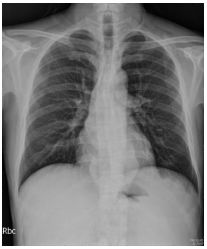

1. A 39-year-old man had this chest X-ray on his health exam. No any clinical symptoms.